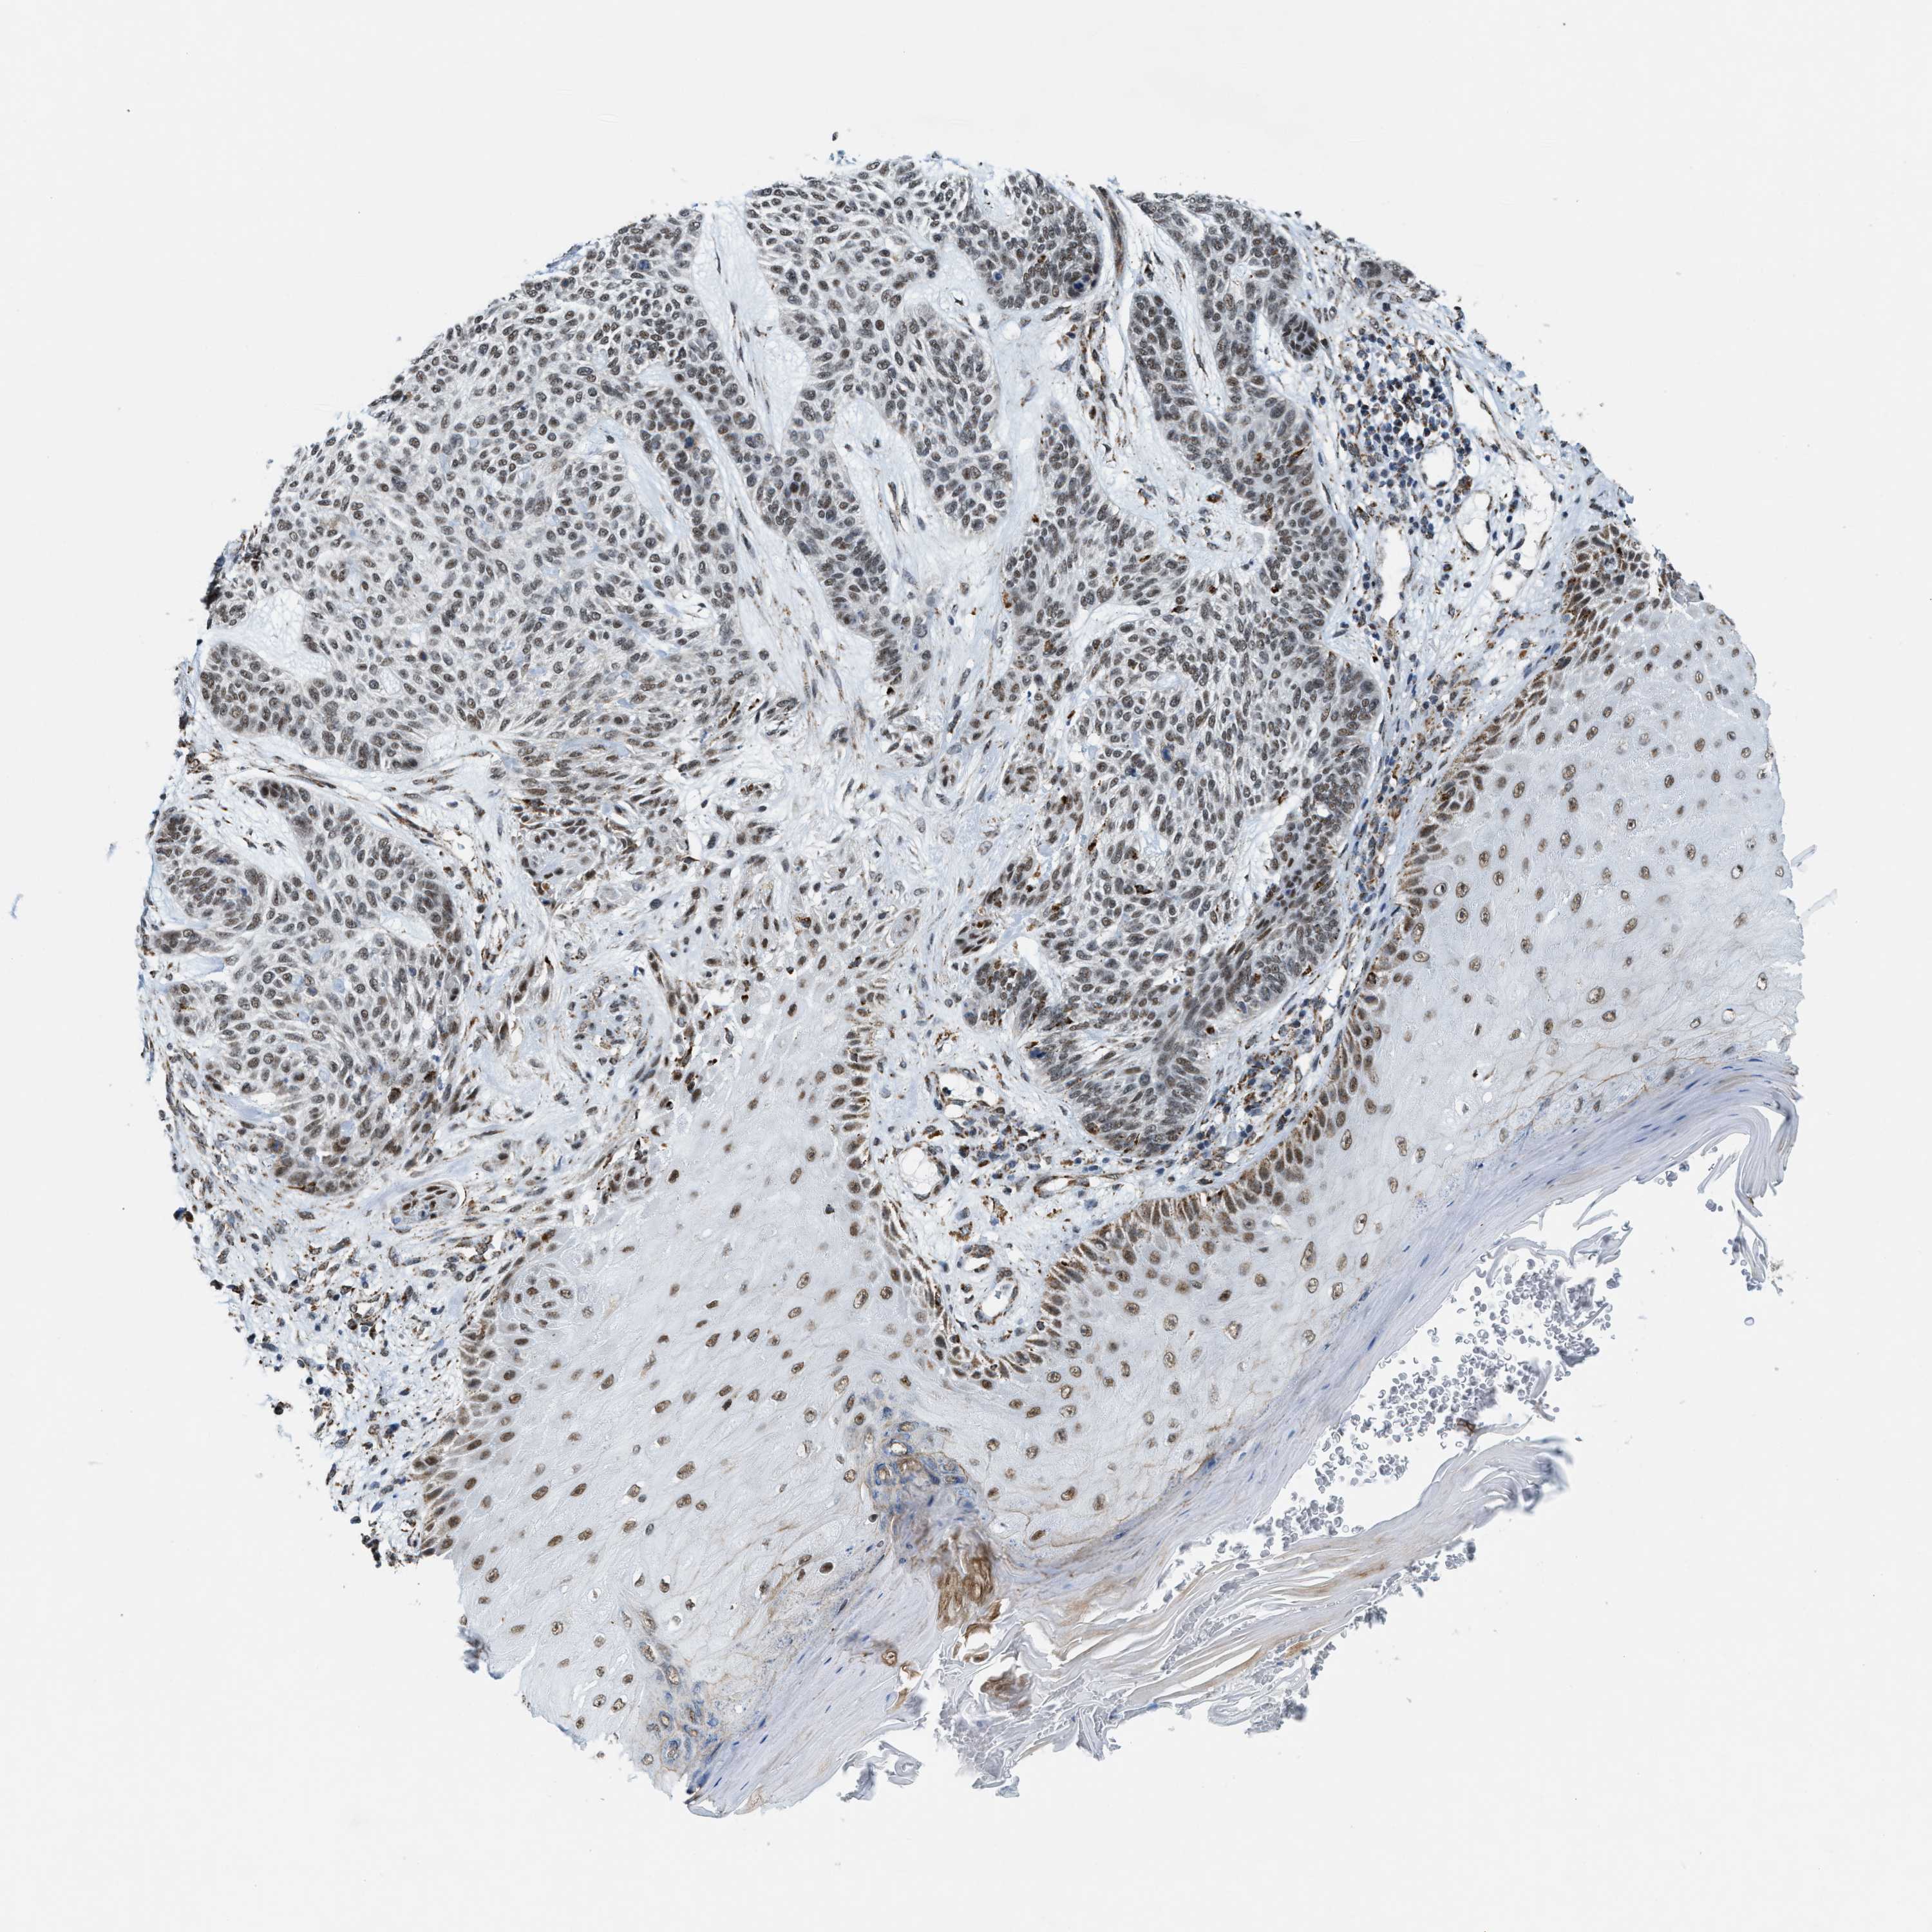

SKIN CANCER - Protein expressioni

A mouse-over function shows sample information and annotation data. Click on an image to view it in a full screen mode. Samples can be filtered based on level of antibody staining by selecting one or several of the following categories: high, medium, low and not detected. The assay and annotation is described here.

Antibody stainingi

Antibody staining in the annotated cell types in the current human tissue is reported as not detected, low, medium, or high, based on conventional immunohistochemistry profiling in selected tissues. This score is based on the combination of the staining intensity and fraction of stained cells.

Each image is clickable and will lead to virtual microscopy that enables deeper exploration of all samples and also displays staining intensity scores, fraction scores and subcellular localization as well as patient and tissue information for each sample.

Antibody HPA019522

Antibody HPA021002

Staining

High

Medium

Low

Not detected

Intensity

Strong

Moderate

Weak

Negative

Quantity

>75%

75%-25%

<25%

None

Location

Nuclear

Cytoplasmic/membranous

Cytoplasmic/membranous,nuclear

Squamous cell carcinoma in situ, NOS

Squamous cell carcinoma, NOS

Squamous cell carcinoma, metastatic, NOS

Basal cell carcinoma